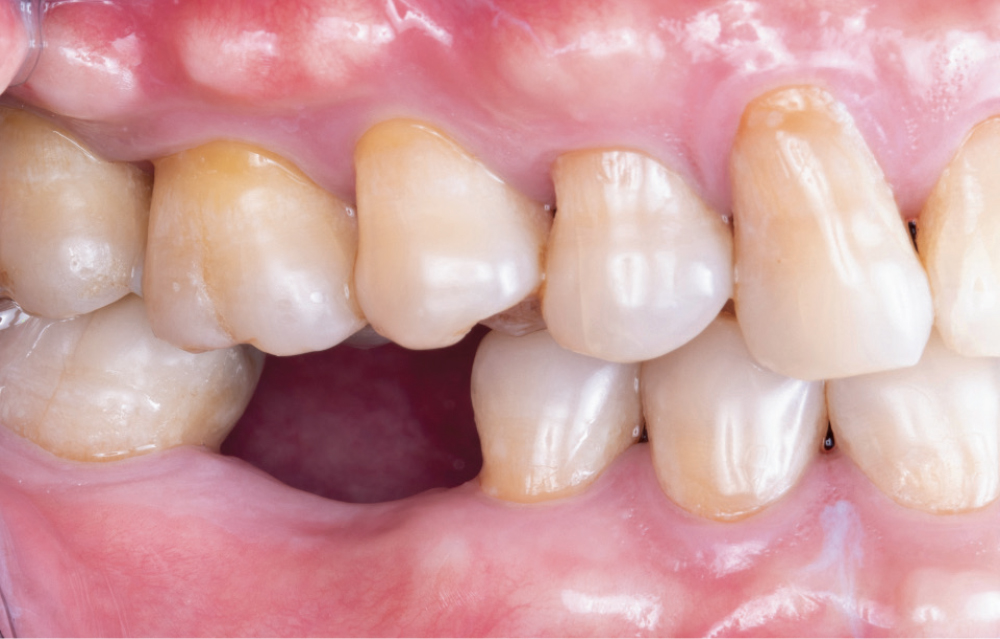

Figures 18a, 18b: The final restoration seated perfectly without the need for any adjustment. The custom healing abutment created an emergence profile that allowed the final restoration to blend seamlessly with the adjacent teeth and appear to emerge from the tissue like a natural tooth. The result blends well with the adjacent dentition, restoring both function and esthetics.